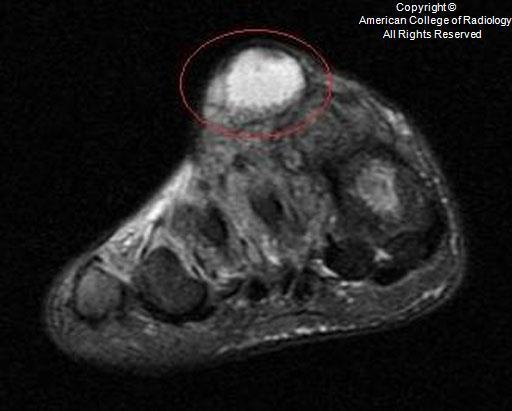

A

Medulla foot

• Medulla region in India

• also called mycetoma

• fungal (eumycetoma)

• bacterial (actinomycetoma)

• commonly seen in those who walk barefoot, such as agricultural workers

• patients typically present with painless swelling and a draining sinus tracts. The purulent discharge typically contains colored “grains” representing clumps of the causative organism

• Stage 0 – Soft-tissue swelling, which can become nodular and expansive.

Stage I – Extrinsic pressure on the bone causing bone displacement or scalloping. No bone involvement.

Stage II – Periosteal reaction or reactive sclerosis as a result of irritation of the bone surface by the causative organism.

Stage III – Bone erosion or cavitation as a result of penetration of the periosteum and cortex.

Stage IV – Joint involvement with longitudinal spread along a ray of metatarsal bone and phalanx.

Stage V – Horizontal spread limited to two rays of bone and confined to the hindfoot, midfoot, or forefoot.

Stage VI – Uncontrolled infection with multidirectional destruction